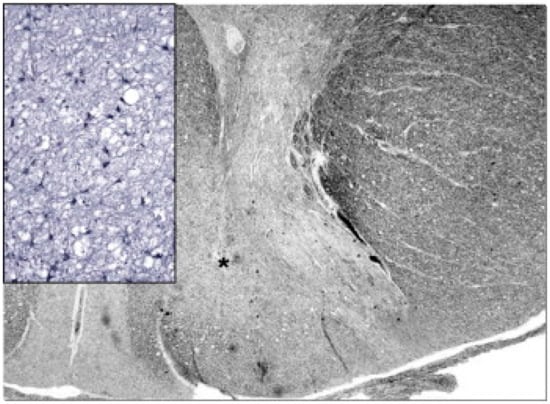

- Oldfors, A.; Fyhr, I.M.; Holme, E.; Larsson, N.G.; Tulinius, M. Neuropathology in Kearns-Sayre Syndrome. Acta Neuropathol. 1990, 80, 541–546. [Google Scholar] [CrossRef]

- Tanji, K.; Vu, T.H.; Schon, E.A.; DiMauro, S.; Bonilla, E. Kearns-Sayre Syndrome: Unusual Pattern of Expression of Subunits of the Respiratory Chain in the Cerebellar System. Ann. Neurol. 1999, 45, 377–383. [Google Scholar] [CrossRef]